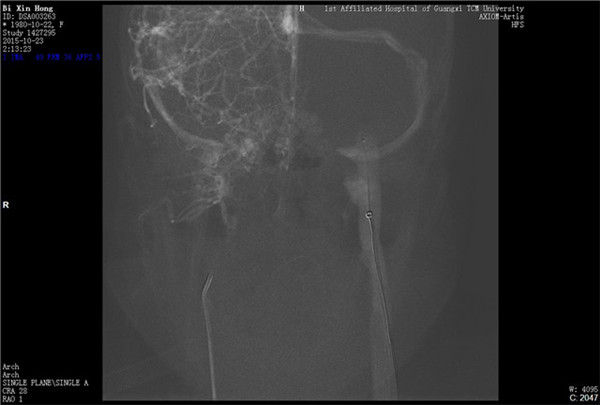

经与患者及家属充分沟通并获得同意后,外六科脑血管病介入治疗团队立即为患者行全脑血管造影,造影结果证实上矢状窦血栓形成,整个上矢状窦完全闭塞,若不采取措施病情很快就会恶化。再次征得家属同意后果断采取微导管介入手术治疗,手术在起病后当晚开始,由于患者血栓位置深在,需要经动、静脉双重途径置管,技术难度较大。术者选取Solitaire支架( 美国 公司)置入微导管远端,释放支架并在原位作短暂停留使支架与血栓充分接触并黏附,一起回撤支架与微导管取出血栓,手术一直持续到第二天凌晨。术后留置导管一条,用于每天以药物继续溶栓。术后患者即清醒,头痛明显缓解,无神经功能缺失。手术第二周时患者已经能够生活自理。2015年12月12日患者痊愈出院。

左颈静脉入路

微导管置入上矢状窦